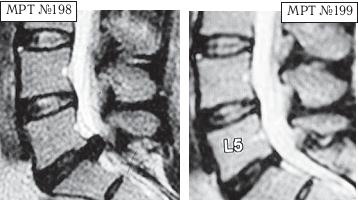

На МРТ № 198 наблюдается состояние поясничного отдела позвоночника: секвестрированная грыжа межпозвонкового диска в сегменте LV—SI абсолютный стеноз спинномозгового канала. На МРТ №199 — состояние поясничного отдела позвоночника после лечения методом вертеброревитологии. Пример № 5.